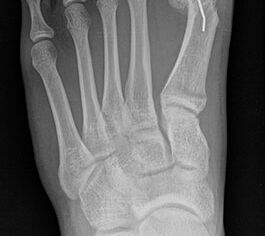

Standard ist die belastete Röntgenaufnahme des Fußes dorso-plantar und seitlich. Günstig ist eine Röhrenkippung von 10°-20°, um die Gelenke der Lisfranc-Linie einsehen zu können.

Ergänzend kann eine Schrägaufnahme hilfreich sein. Bei Metatarsalgien oder Pathologien der Sesambeine liefert die Sprinteraufnahme zusätzliche Informationen. Bei einer Pes planovalgus Fehlstellung wird ergänzend ein Saltzman view durchgeführt.

• Hallux valgus Winkel

• Hallux valgus interphalangeus Winkel

• Intermetatarsalwinkel I zu II

• Distaler Metatarsale Gelenkwinkel (PASA)

• Form des Mittelfußknochenkopfes

• Winkel Metatarsale I Basis zum Os cuneiforme mediale

• Metatarsalindex

• Elevation/ Plantarisierung I. Strahl

• Pes metatarsus adductus

• Wachstumsfugen

• Coalitiones

• Akzessorische Knochen